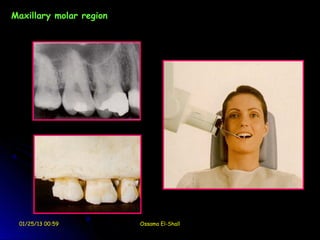

film in center of palate

Maxillary molar region

01/25/13 00:59          Ossama El-Shall

Maxillary Molar

film equidistant from lingual

film centered on

surfaces of teeth (red

second molar

arrows); this opens contacts

between the teeth.

01/25/13 00:59            Ossama El-Shall   film in center of palate